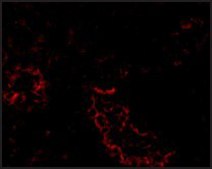

immunofluorescence: suitable, immunohistochemistry: suitable, indirect ELISA: suitable, western blot: suitable